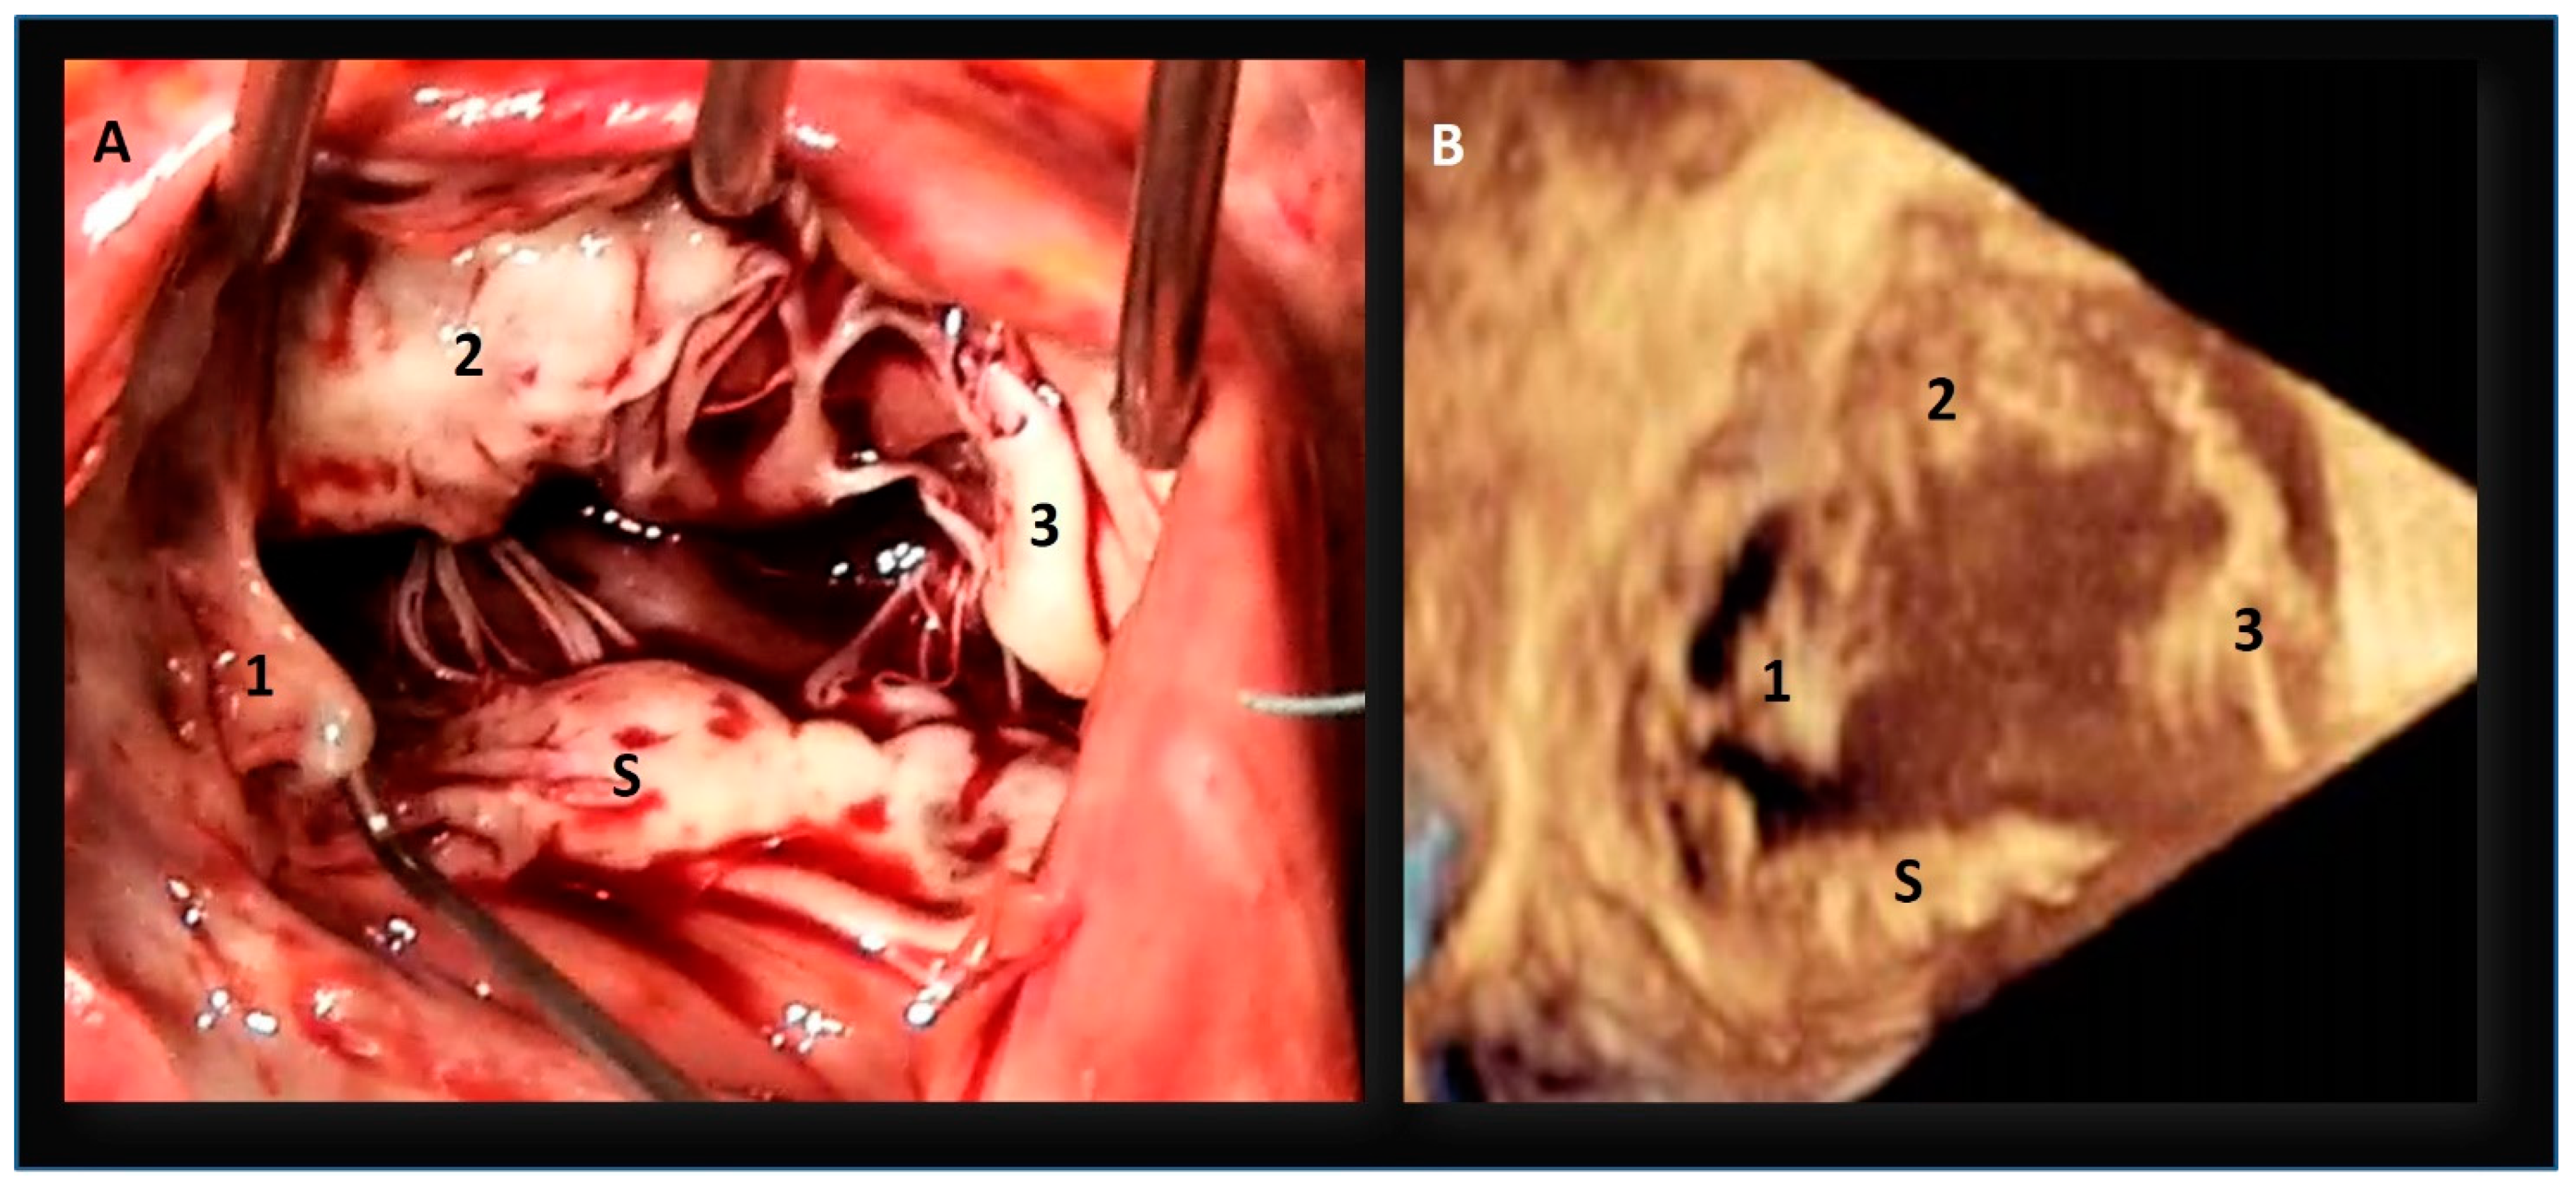

The “Mural” Annulus

4. The “Septal” Annulus

5. Physiological and Physiopathologic Consequences of the Annular Structure